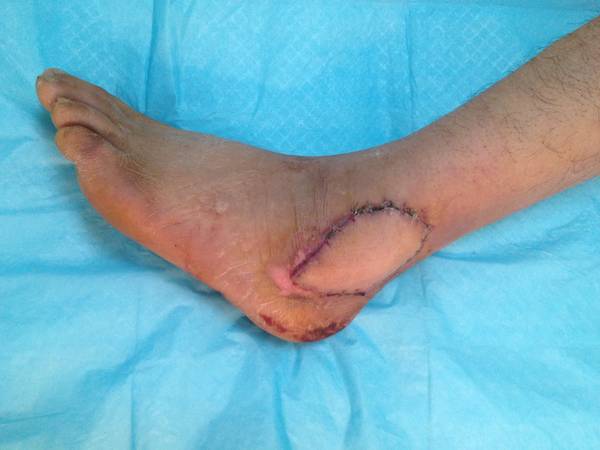

修复术后